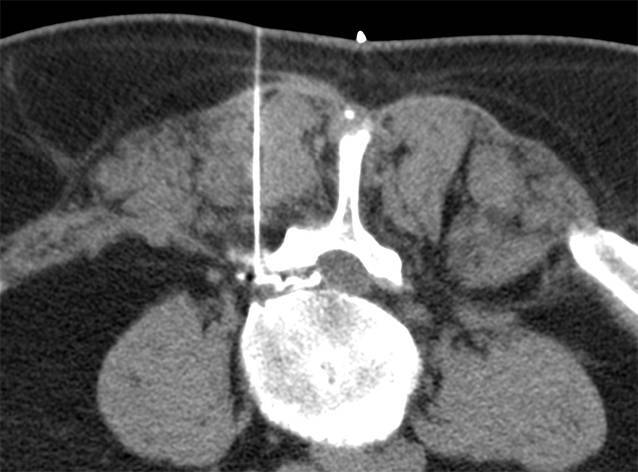

Alle Interventionen wurden in Bauchlage durchgeführt. Die Planung der Untersuchung erfolgte jeweils an einem angepassten Planungsscout auf der zuvor bekannten Interventionshöhe. Anschließend wurde die Interventionsplanung in der entsprechenden CT-Schicht durchgeführt. Nach sorgfältiger lokaler Desinfektion, steriler Vorbereitung und Markierung der Punktionsstelle wurde unter CT-Kontrolle in Low-dose-Technik unter Einsatz von CareDose die Intervention durchgeführt (Tab. 1). Nach Maßgabe des behandelnden Radiologen erfolgte die Überprüfung der Nadelposition während der Intervention, und die Verteilung des Medikamentengemisches wurde dokumentiert (Abb. 1 und 2). Die Interventionen wurden entweder an einem Siemens Emotion 6, an einem Siemens Somatom Definition 64 oder an einem Siemens Definition AS 64 durchgeführt.

In Abhängigkeit von der körperlichen Fülle des Patienten wurde eine 22G-Nadel mit einer Länge von 90 mm oder 120 mm verwendet (Becton Dickinson SA, S. Agustin del Gualdix, Spain). Als Lokalanästhetikum wurde 2 %iges Meaverin eingesetzt (Meaverin 2 %, Puren Pharma, Munich, Germany). Als Kontrastmittel zur Dokumentation der Verteilung des Medikamentengemisches wurde Iohexol (Accupaque 240, GE Healthcare, Munich, Germany) verwendet, als Kortikoid wurden in Abhängigkeit vom Patientengewicht, Verträglichkeit sowie Vorerkrankungen 10–20 mg Triamcinolon injiziert (Volon A, (2 ×) 10 mg, Dermapharm AG, Gruenwald, Germany). Nach der Durchführung der Intervention wurden die Patienten gebeten, jeweils eine Stunde im Institut zu verweilen. Die anschließende Verabschiedung erfolgte vom durchführenden Arzt, um sicherzustellen, dass keine Nebenwirkungen aufgetreten sind. Unmittelbar nach der Therapie und im Abstand von 1 bis 14 Tagen (Durchschnitt: 8 Tage) wurde erneut der Schmerzscore mittels VAS bestimmt.